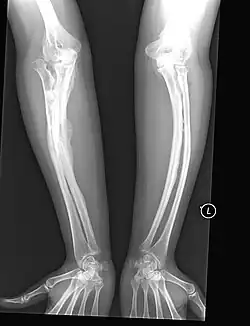

Orthopedic

The main symptom of osteogenesis imperfecta is fragile, low mineral density bones; all types of OI have some bone involvement.[5] In moderate and especially severe OI, the long bones may be bowed, sometimes extremely so.[28] The weakness of the bones causes them to fracture easily—a study at the Endocrine Unit at the National Institute of Child Health in Karachi, Pakistan found an average of 5.8 fractures per year in untreated children.[29] Fractures typically occur much less after puberty, but begin to increase again in women after menopause and in men between the ages of 60 and 80.[1]: 486

- Type V – Having the same clinical features as type IV, it can be clinically distinguished by observing a "mesh-like" appearance to a bone biopsy under a microscope. Type V can be further distinguished from other types of OI by the "V triad": an opaque band (visible on X-ray) adjacent to the growth plates; hypertrophic calluses (abnormally large masses of bony repair tissue) which form at fracture sites during the healing process; and calcification of the interosseous membrane of the forearm,[50] which may make it difficult to turn the wrist.[1]: 429 Other features of this condition may include pulled elbow, and, as in other types of OI, long bone bowing and hearing loss.[64] Cases of this type are caused by mutations in the IFITM5 gene on chromosome 11p15.5.[64][49] The separation of type V from type IV OI, its clinical type, was initially suggested even before its genetic cause was known, by Glorieux et al. in 2000.[50][65] Type V is relatively common compared to other genetically defined types of OI—4% of OI patients at the genetics department of the Brazilian Hospital de Clínicas de Porto Alegre were found to have it.[66]

Diagnosis is typically based on medical imaging, including plain X-rays, and symptoms. In severe OI, signs on medical imaging include abnormalities in all extremities and the spine.[97] As X-rays are often insensitive to the comparatively smaller bone density loss associated with type I OI, DEXA scans may be needed.[5]: 1514